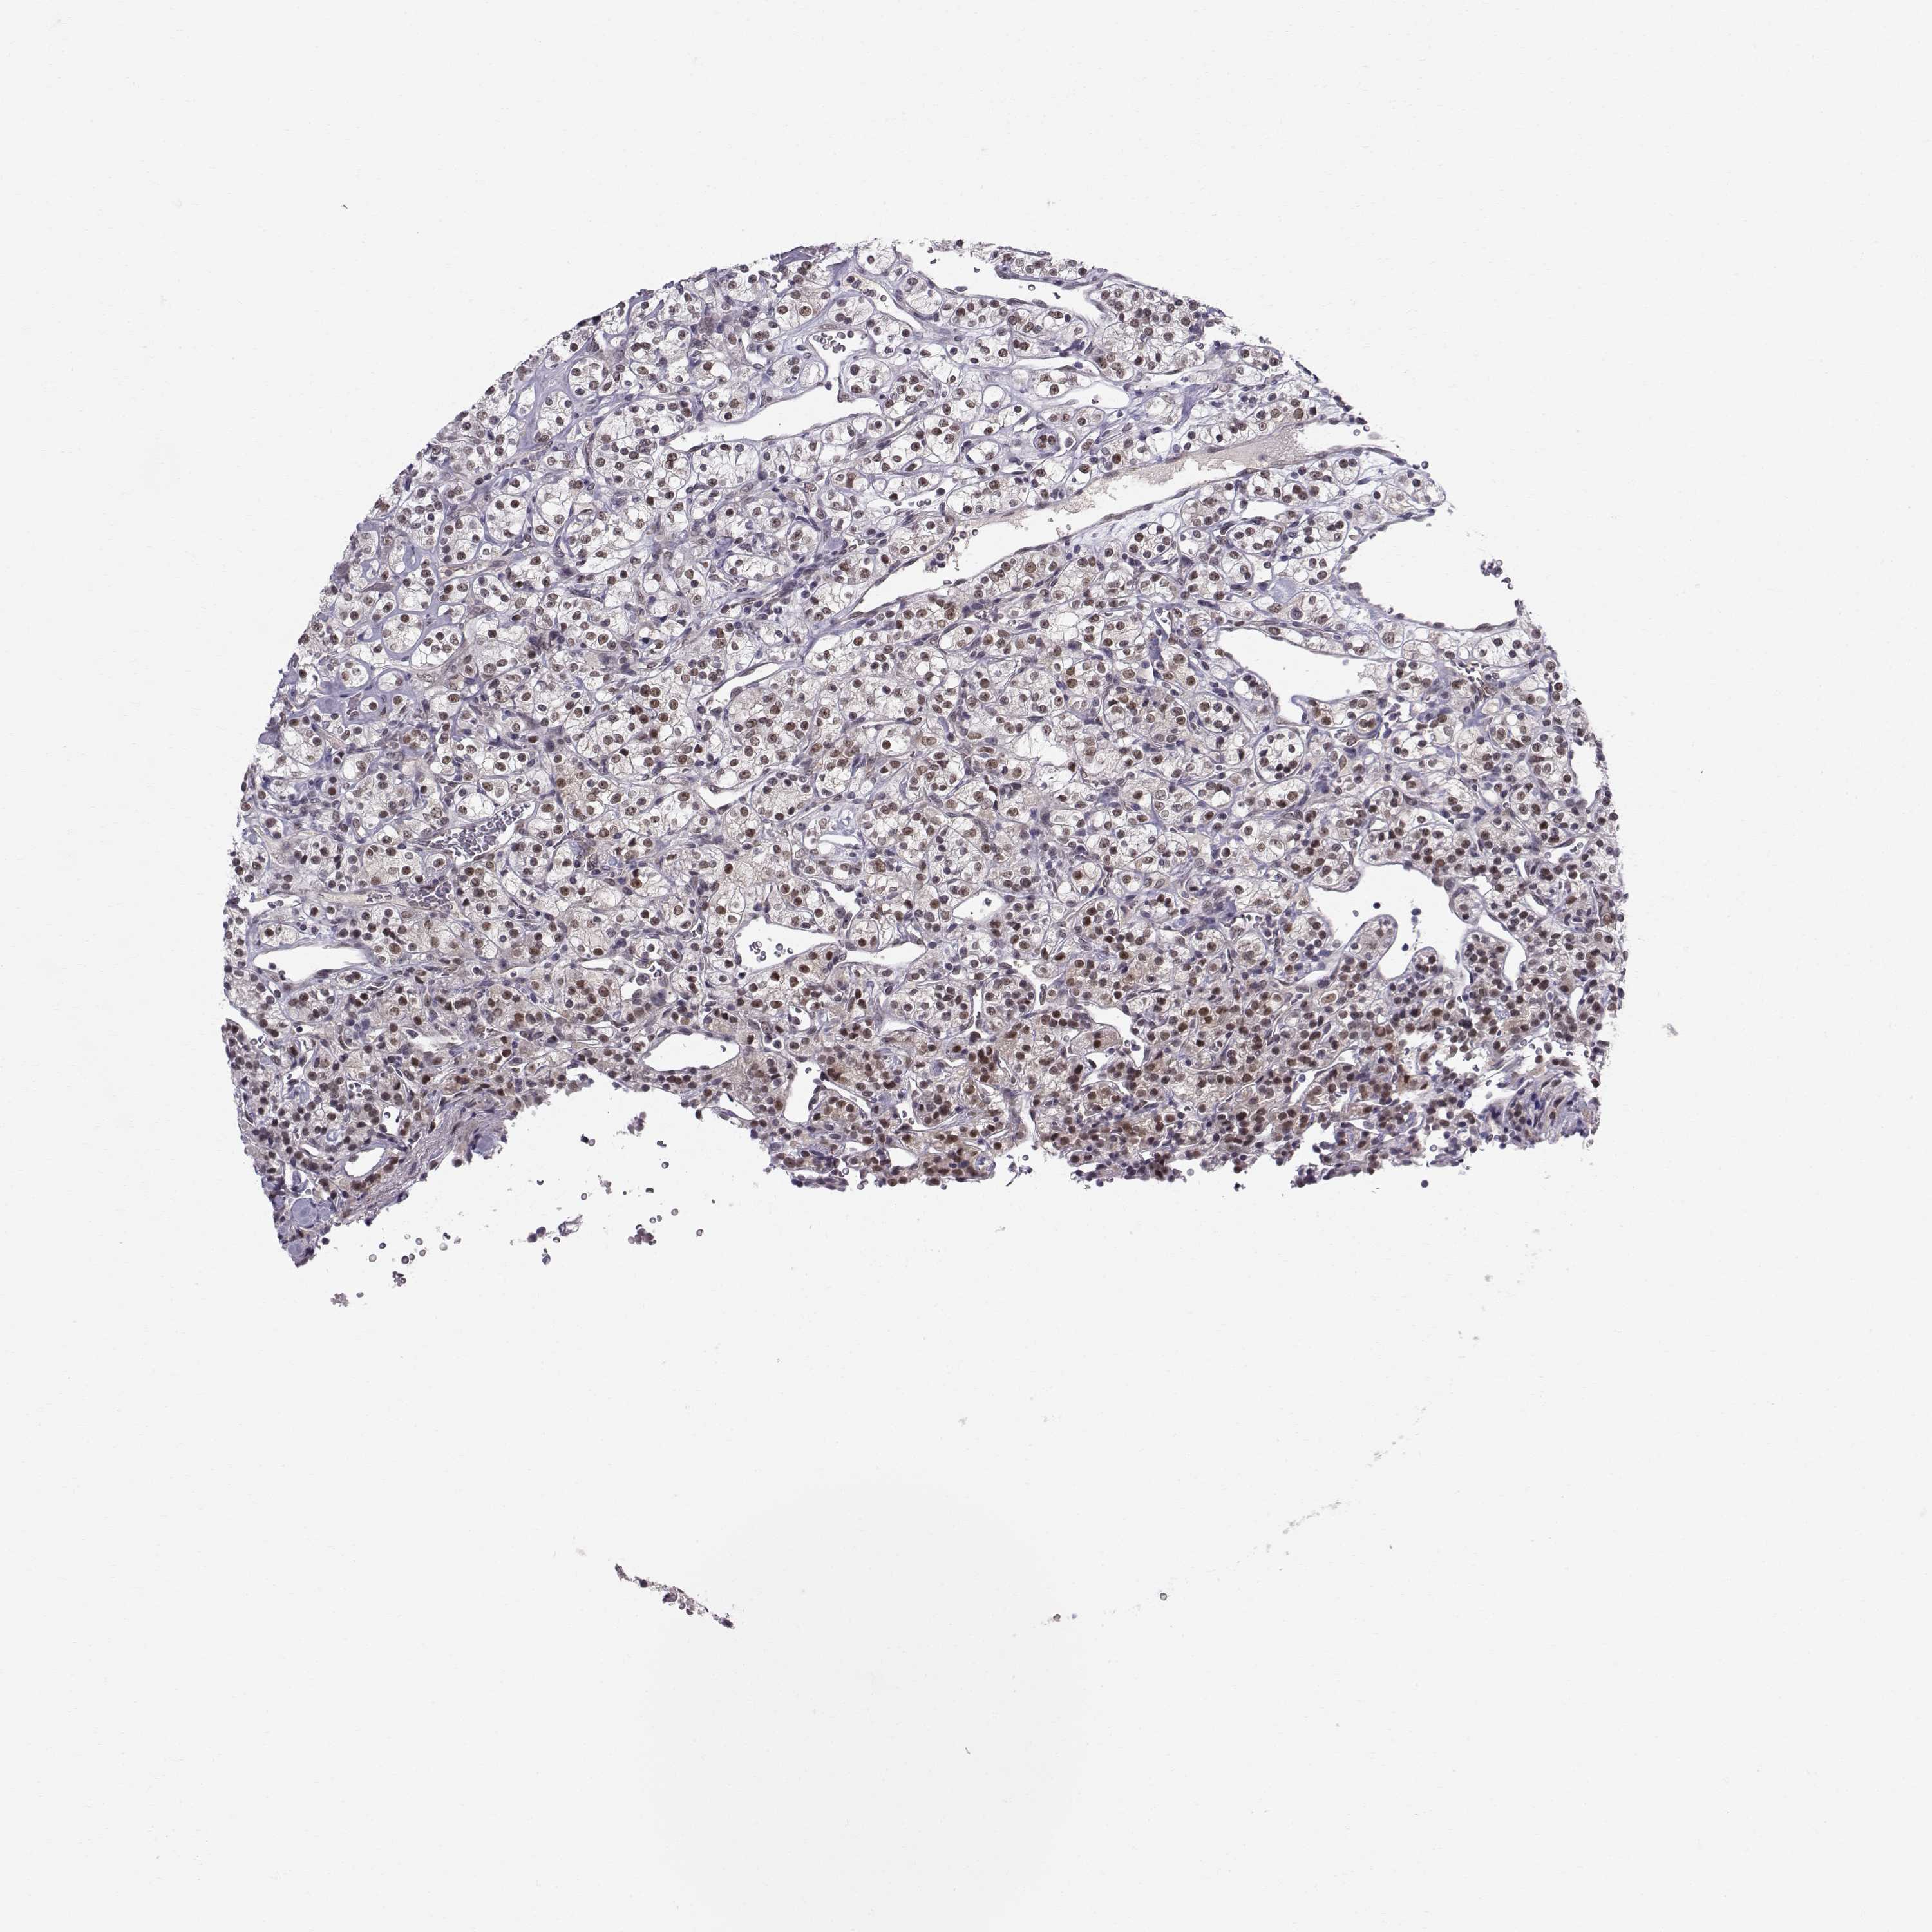

KIDNEY RENAL CLEAR CELL CARCINOMA (VALIDATION) - Interactive survival scatter ploti

The Survival Scatter plot shows the clinical status (i.e. dead or alive) for all individuals in the patient cohort, based on the same data that underlies the corresponding Kaplan-Meier plots. Patients that are alive at last time for follow-up are shown in blue and patients who have died during the study are shown in red.

The x-axis shows the expression levels (FPKM) of the investigated gene in the tumor tissue at the time of diagnosis. The y-axis shows the follow-up time after diagnosis (years). Both axes are complimented with kernel density curves demonstrating the data density over the axes. The top density plot shows the expression levels (FPKM) distribution among dead (red) and alive patients (blue). The right density plot shows the data density of the survived years of dead patients with high and low expression levels respectively, stratified using the cutoff indicated by the vertical dashed line through the Survival Scatter plot. This cutoff is automatically defined based on the FPKM cutoff that minimizes the p-score. The cutoff can be changed by dragging the vertical line or by entering a cutoff value in the square labeled "Current cut-off".

Under the Survival Scatter plot the p-score landscape (black curve; left axis) is shown together with dead median separation (red curve; right axis). Dead median separation is the difference in median mRNA expression between patients who have died with high and low expression, respectively. It is calculated as follows: median FPKM expression of dead patients with high expression - median FPKM expression of dead patients with low expression. This is intended to aid the user in visually exploring custom cutoffs and the associated p-scores and dead median separation.

Individual patient data is displayed and can be filtered by clicking on one or more of the category buttons on the top of the page. Categories describing expression level and patient information include: high, low, alive, dead, female, male and tumor stages. The scale of the x-axis can be toggled between linear and log-scale by clicking on the "x log" button. Mouse-over function shows TCGA ID, patient information and mRNA expression (FPKM) for each patient.

& Survival analysisi

Kaplan-Meier plots summarize results from analysis of correlation between mRNA expression level and patient survival. Patients were divided based on level of expression into one of the two groups "low" (under cut off) or "high" (over cut off). X-axis shows time for survival (years) and y-axis shows the probability of survival, where 1.0 corresponds to 100 percent.

RPP38 is not prognostic in Kidney Renal Clear Cell Carcinoma (validation)

: 20.7

Average pTPM 17.2

Number of samples 100